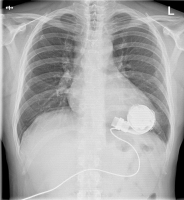

Abbildung 1: Postoperatives Thoraxröntgen des Patienten

LVAD

Thoraxröntgen